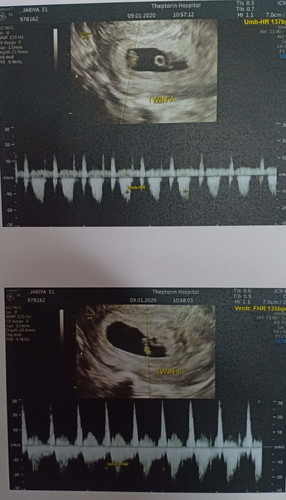

ท้องแฝด3 ใครมีวิธีแก้แพ้ท้องยังไงบ้างค่ะ ตอนนี้ได้7 สัปดาห์ค่ะ

ท้องแฝด3 อาการแพ้ท้อง